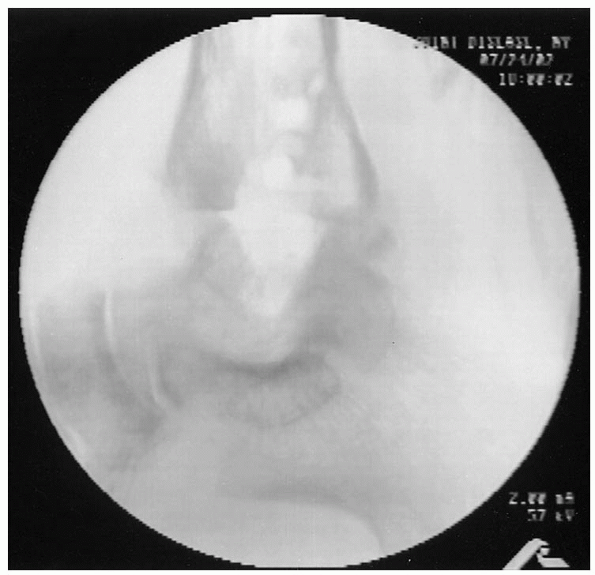

FIGURE 32-2. Anteroposterior (A), lateral (B), and mortise (C) preoperative radiographs.

bone grafting usually is necessary. A standard radiographic ankle

trauma series, including anteroposterior, lateral, and mortise views,

is required to assess the joint (Fig. 32-2). Standing views may offer a better picture of the clinical situation.